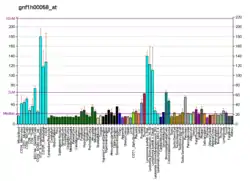

Protein SCO1 homolog, mitochondrial, also known as SCO1, cytochrome c oxidase assembly protein, is a protein that in humans is encoded by the SCO1 gene.[5][6] SCO1 localizes predominantly to blood vessels, whereas SCO2 is barely detectable, as well as to tissues with high levels of oxidative phosphorylation. The expression of SCO2 is also much higher than that of SCO1 in muscle tissue, while SCO1 is expressed at higher levels in liver tissue than SCO2. Mutations in both SCO1 and SCO2 are associated with distinct clinical phenotypes as well as tissue-specific cytochrome c oxidase (complex IV) deficiency.[7][8][9]

Mammalian cytochrome c oxidase (COX) catalyzes the transfer of reducing equivalents from cytochrome c to molecular oxygen and pumps protons across the inner mitochondrial membrane. In yeast, 2 related COX assembly genes, SCO1 and SCO2 (synthesis of cytochrome c oxidase), enable subunits 1 and 2 to be incorporated into the holoprotein. This gene is the human homolog to the yeast SCO1 gene.[6] It is predominantly expressed in muscle, heart, and brain tissues, which are also known for their high rates of oxidative phosphorylation.[5] SCO1 is a copper metallochaperone that is located in the inner mitochondrial membrane and is important for the maturation and stabilization of cytochrome c oxidase subunit II (MT-CO2/COX2). It plays a role in the regulation of copper homeostasis by controlling the localization and abundance of CTR1 and is responsible for the transportation of copper to the Cu(A) site on MT-CO2/COX2.[12][8][9][13]